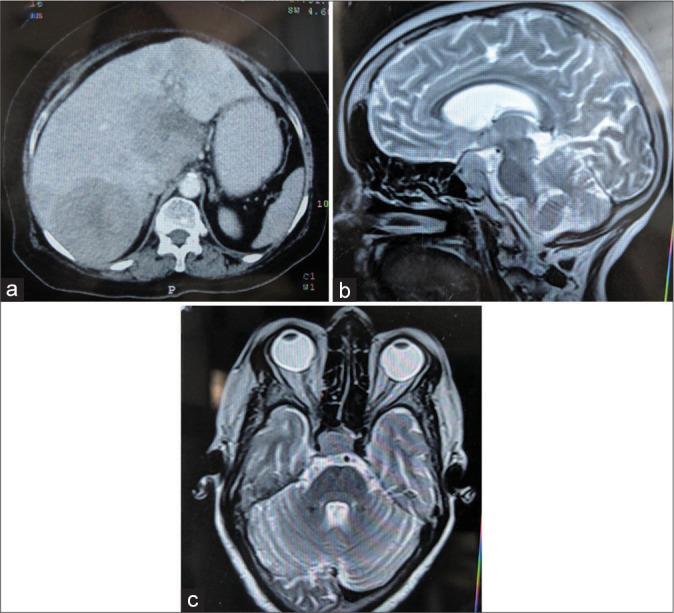

Pituitary carcinomas (PCs) are rare entities constituting about 0.1-0.2% of all pituitary neoplasms. They are diagnosed by the presence of craniospinal or systemic metastasis in pituitary adenomas (PAs). The distant metastatic sites include liver, followed by bone, lung, and lymph nodes. The diagnosis of PC is rarely made on fine-needle aspiration cytology (FNAC) with only six cases reported till date; hence, the cytologic features are not well defined. Herein, we report a case of PA having high Ki-67 proliferation index and p53 expression, presenting with liver lesion 6 weeks post-surgery and diagnosed on FNA. Detailed cytomorphologic features are defined and compared. We emphasize that FNAC, along with clinic-radiologic correlation, is a cost-effective, safe, and diagnostically accurate method of diagnosing PC metastases.

垂体癌(PCs)是罕见的实体肿瘤,约占所有垂体肿瘤的0.1 - 0.2%。它们通过垂体腺瘤(PAs)中出现颅脊髓或全身转移来诊断。远处转移部位包括肝脏,其次是骨骼、肺部和淋巴结。垂体癌的诊断很少通过细针穿刺细胞学检查(FNAC)做出,迄今为止仅报道了6例;因此,细胞学特征尚未明确界定。在此,我们报告一例垂体腺瘤,其Ki-67增殖指数和p53表达较高,术后6周出现肝脏病变,并通过细针穿刺抽吸活检(FNA)确诊。详细的细胞形态学特征得以明确并进行了比较。我们强调,FNAC结合临床-放射学相关性,是一种经济有效、安全且诊断准确的诊断垂体癌转移的方法。